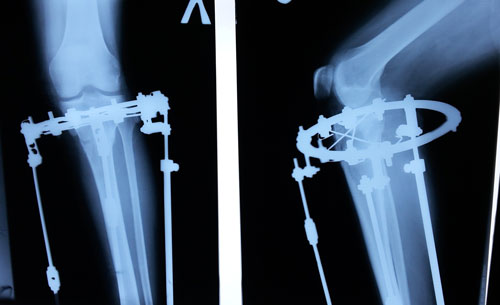

Рентген в 62 дня.

Сращение идёт отлично для этого срока и возраста пациентки.